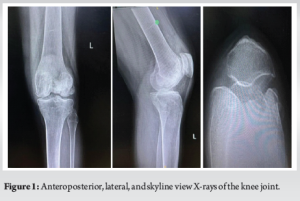

A midline incision using the conventional medial parapatellar approach to the knee was made. Intraoperative examination revealed fissuring and loss of articular cartilage with alteration in the morphology of both medial and lateral femoral condyles (Fig. 6). Large articular cartilage dehiscence with defect noted in the lateral femoral condyle (Fig. 7). A loose bodymeasuring around 5 × 3 cm was retrieved from the lateral femoral gutter. Intraoperative tissue samples were sent for histopathological examination, which later confirmed the diagnosis of chronic synovitis with bone osteonecrosis. Femoral and tibial marker pin inserted and bony registration done. Gap balancing using a robotic-assisted system (CUVIS® Robotic Joint System) was done. The cuts were performed according to the gap-balancing principles to attain perfect mechanical alignment and balance mediolateral gaps in all ranges of movements from full extension to full flexion, which were assessed in real-time by the robot. The trial prosthesis was inserted, and kinematics were tested, including patellofemoral joint tracking. The final implantation was done using cemented femoral components of size H, tibial components of size 5, and a fixed bearing tibial insert of 9 mm thickness (Maxx Freedom TKA System, Meril®, IN). The mediolateral and AP stability, along with patella tracking, were ascertained during trial and after final implantation. No major complications, such as infection, wound breakdown, deep venous thrombosis, or vascular injury, occurred. The post-operative radiograph revealed a well-aligned and well-fixed prosthesis (Fig. 8). The patient was made to walk comfortably on the same day and was very satisfied with the final outcome. At the latest 3rd-month follow-up, the radiographs showed a well-fixed prosthesis (Fig. 9). The patient had a stable knee with a good range of motion of 0–110° (Fig. 10) with OKS of 42, KSS-K score of 88, and KSS-F score of 90, which had improved significantly compared to the pre-operative recorded score.